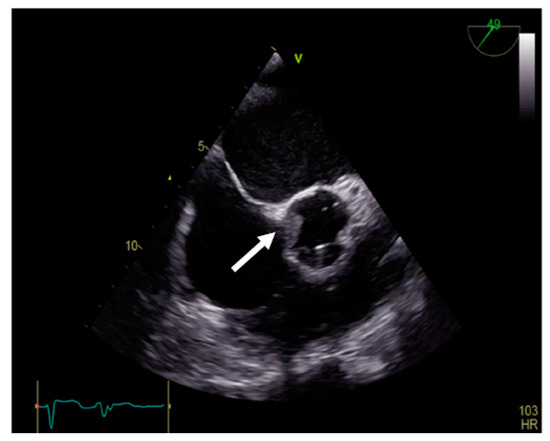

The mobility of the discs and the presence of pathological features such as thrombus, pannus, or vegetation are evaluated using bidimensional echocardiography. The thrombus can sometimes be difficult to visualize; in some cases, it appears as an echodense mass that is located on the discs and restricts their motion (Figure 2A) [17]. The colour Doppler flow quantification may reveal a turbulent flow above the valve or even the absence of colour flow through the prosthesis (Figure 2B). While 2D imaging leaves room for ambiguity in terms of thrombus localization in relation to the prosthesis, 3D images clearly reveal the relationship between them, as illustrated in the moving images of Video S1 (Supplementary Material). The evaluation of intracardiac masses suspected for thrombi using pulsed wave (PW) tissue Doppler imaging (TDI) might be an improvement over visual assessment, as it provides a more precise definition of mass mobility [18,19].

Figure 2.

(A) TTE. Prosthetic mitral valve PLAX thrombus on the disc left atrial side (arrow). (B) TTE. Colour Doppler turbulent flow above the prosthesis (arrow).